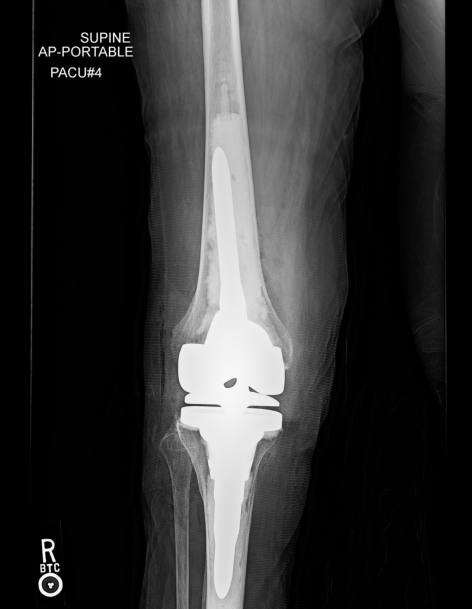

In May 2024, I did have the surgery and feel fortunate that it has worked so well. My leg is straighter than it’s ever been with hyperextending and minimum pain after the surgery. I am still going to PT (it’s been a month since the surgery), but thanks to the experience and continuing studies of Dr. Shen, I am progressing without constantly feeling my knee buckling and fearing I will fall because knee could collapse. Dr. Shen continues to be kind and considerate and interested in how I am coming along and encouraging me (not always the case after other surgeries). He does not close the book on you once surgery is finished but control help you achieve best outcome going forward. Thank you Dr. Shen, it’s truly a miracle to have a straight and stable leg!

I am blessed to have found you when others turned me away as a hopeless case.